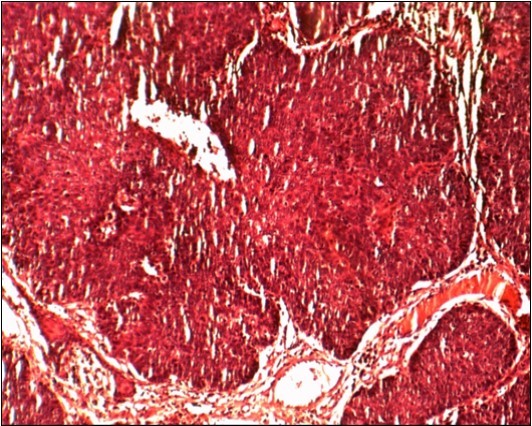

All 23 patients presented invasive differentiated squamous cell carcinoma (Figure 3). None in situ carcinoma was found.

Figure 3.Imature Squamous cell carcinoma ,Hématein Eosin Coloration (HEX100):Epideremoid growth pattern without kératization